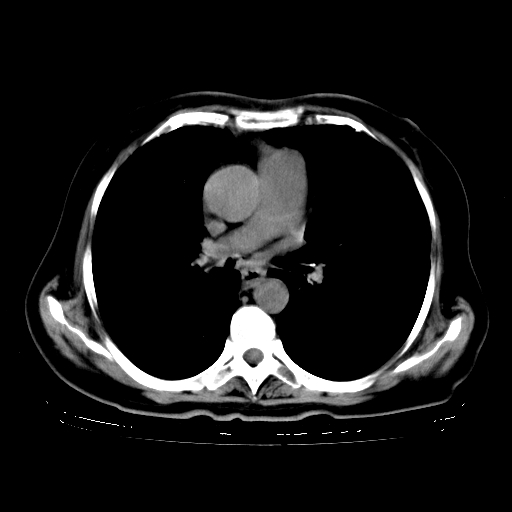

2.胸主动脉夹层。

4、主动脉夹层。

5、右侧少量胸腔积液。

支持,首先一元论解释。胸主动脉部分层面环形低密度,中心强化。环形影不强化。不象真假腔的改变。我考虑动脉炎,不太支持夹层动脉瘤-和大家的观点不一致,希望楼主让患者再做个心血管的彩超吧。

继发型肺结核,右下肺支气管内膜结核.右侧少量胸腔积液.主动脉夹层.